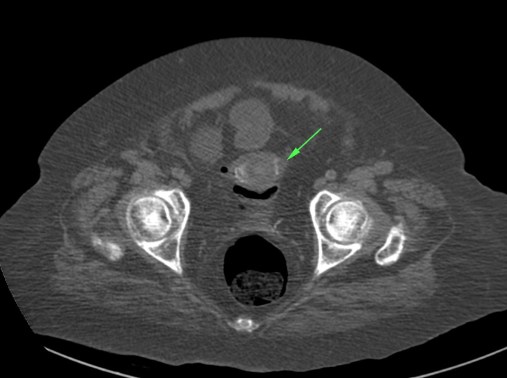

Se realiza placa de abdomen y TC en vacío y fase portal.

El cuadro oclusivo está producido por una litiasis biliar que ha pasado de la vesícula al intestino a través de una fístula con el duodeno y que llegó hasta el recto por una insuficiencia de la válvula ileocecal. Así, se produjo una dilatación generalizada de asas, principalmente de las del intestino grueso, que finalmente derivó en isquemia intestinal.